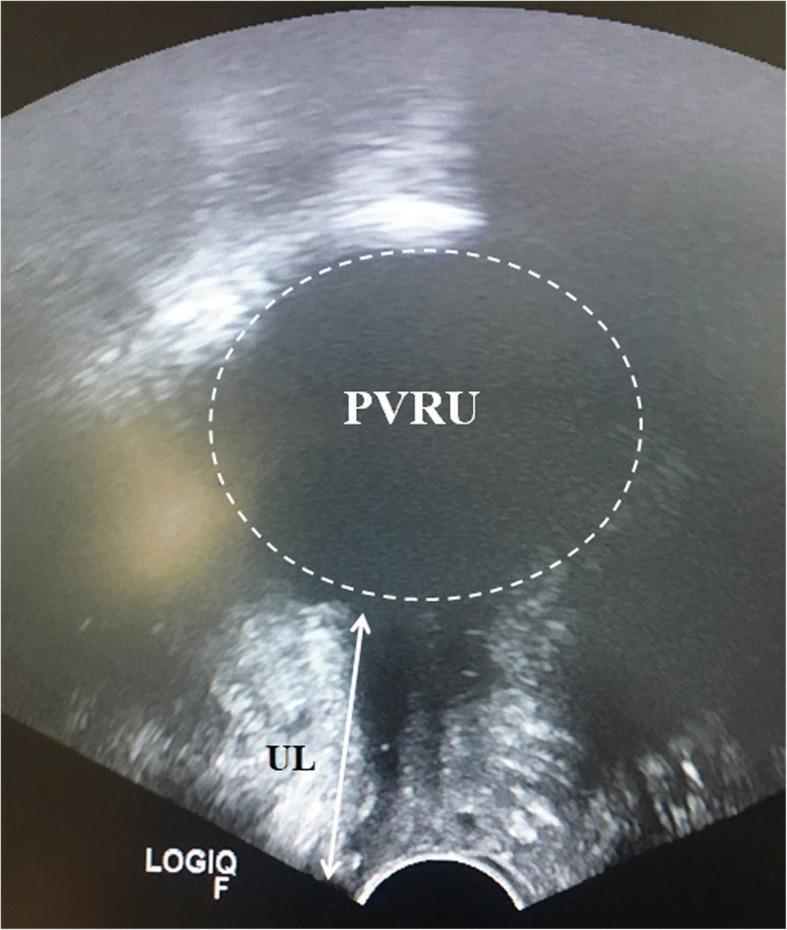

A 79-year-old Caucasian woman presented to our institute with urgency (12-15 times/day), nocturia (3 times/night), and reoccurring urinary tract infections. A physical examination revealed no anatomical malformation in her genital organs, 150 mL post-void urine retention, and a significant narrowing in the mid-segment of the urethra (4 mm). After informed consent, our patient underwent urethral dilatation ranging from Ch9 (3 mm) to Ch39 (13 mm), and reported no symptoms at the 4-week follow-up, with no post-void residual urine.

一名79岁的白人女性因尿急(每天12 - 15次)、夜尿(每晚3次)和反复尿路感染前来我院就诊。体格检查发现其生殖器官无解剖畸形,排尿后残余尿量为150 mL,尿道中段明显狭窄(4 mm)。在获得知情同意后,我们的患者接受了从Ch9(3 mm)到Ch39(13 mm)的尿道扩张,4周随访时报告无症状,且无排尿后残余尿。